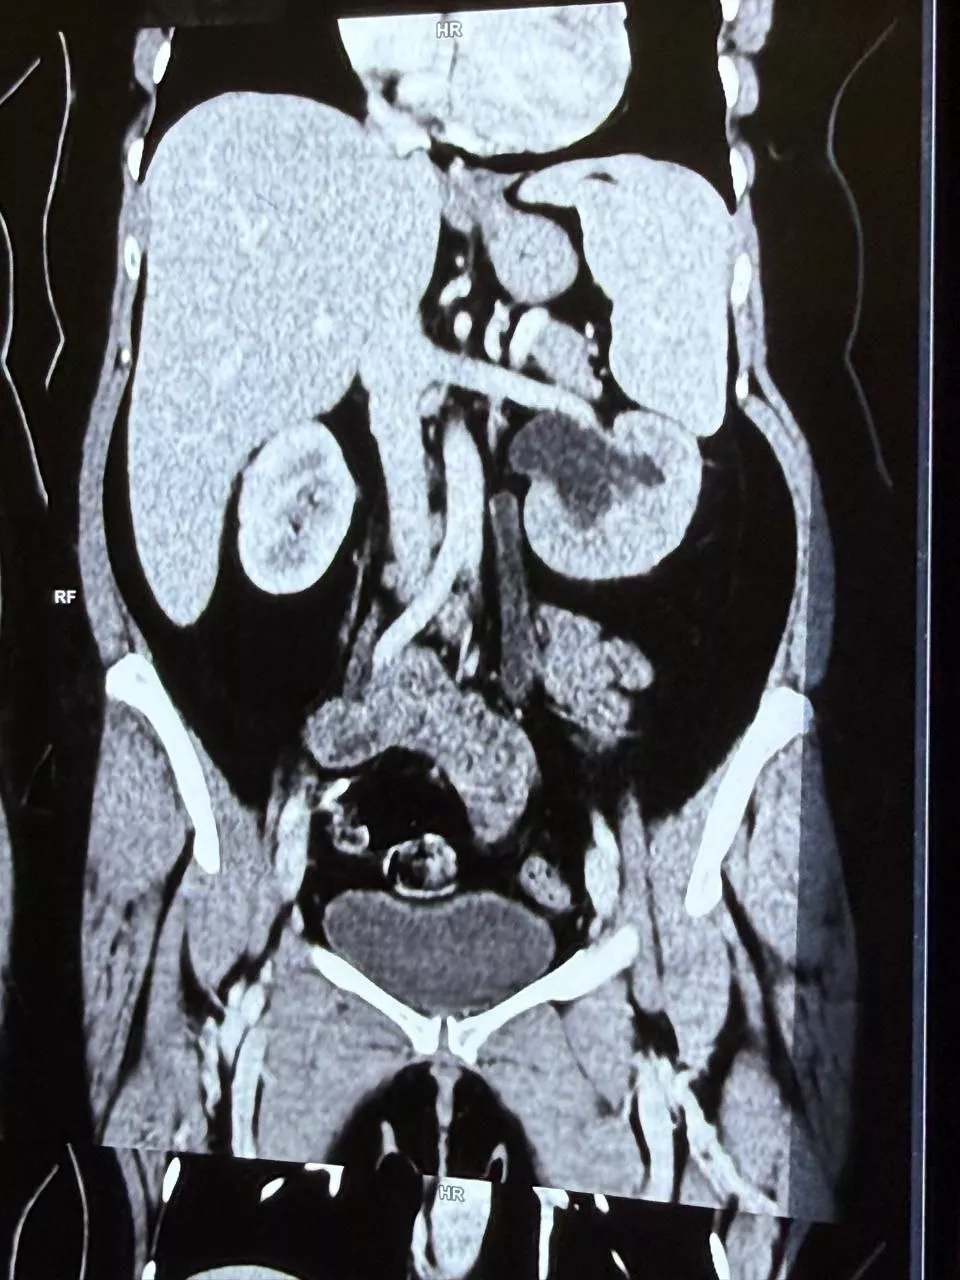

Case Presentation: We report the case of a 46-year-old woman who developed continuous urinary incontinence two days after undergoing TLH. Drain showed increased amount of fluid drainage which raised suspicion of urinary leak. Drain fluid analysis showed raised Sr. Creatinine . CT Imaging confirmed a distal left ureteric injury with uretero-vaginal fistula. Initial management with Double-J (DJ) ureteric stenting resulted in temporary improvement; however, symptoms of urinary incontinence with intermittent voiding was observed after stent removal. Definitive management with ureteroneocystostomy was performed, leading to complete resolution of symptoms and preservation of renal function.

Ultrasonography showed mild left-sided hydroureteronephrosis. Contrast-enhanced CT urography demonstrated contrast extravasation from the distal left ureter into the vaginal vault. Cystoscopy revealed normal bladder mucosa without evidence of vesicovaginal fistula. Retrograde pyelography confirmed distal ureteric injury with uretero-vaginal fistula .